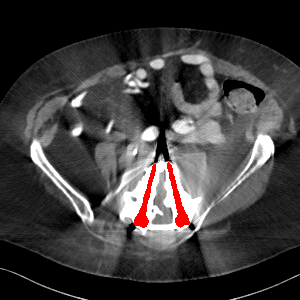

Visual comparison. As shown in Fig. 5, metallic implants such as spinal rods and hip prosthesis cause severe streaky artifacts and metal shadows, which obscure bone structures around them. cGan-CT cannot recover image intensity correctly for both cases. Sinogram domain or dual-domain methods perform much better than cGan-CT. LI, NMAR, and CNNMAR introduce strong secondary artifacts and distort the whole images. In NMAR images, there are fake bone structures around the metals, which is related to segmentation error in the prior image from strong metal artifacts. The segmentation error is also visible in NMAR sinogram. CNNMAR cannot restore the correct bone structures between rods in case 1. The tissues around the metals are over-smoothed in DuDoNet because LI sinogram and image are used as inputs, and the missing information cannot be inferred later. Our model retains more structural information than DuDoNet and generates anatomically more faithful artifact-reduced images.

Visual comparison. Fig. 7 shows two clinical CT images with metal artifacts. Case 1 is with moderate metal artifacts. cGan-CT does not suppress the artifacts completely and generates some fake details. LI, NMAR, CNN-MAR remove all the artifacts but introduce new streak artifacts, which is caused by the discontinuity in the corrected sinogram. DuDoNet outputs over-smoothed sinogram, which leads to blurred tissues close to the metal implants, such as muscle and bone. Only our model can provide realistic enhanced sinogram and remove the artifacts while retaining the structure of nearby tissues. Case 2 is very challenging as the rods bring strong metal shadows and bright artifacts around the vertebra. cGan-CT recovers the shape of vertebra but changes the overall image intensity. Other sinogram inpainting methods fail as the soft tissue and bone near the rods are heavily distorted. Our model removes part of the dark bands and reproduces correct anatomical structures around the rods.